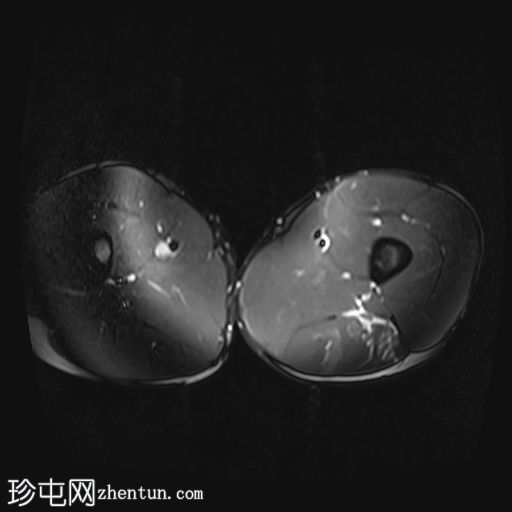

矢状位

STIR序列

股二头肌长头近端和中段可见高信号水肿,大小约10×3厘米。

此外,邻近的半腱肌可见羽毛状水肿,大小约5×2厘米。

未见肌内积液或血肿。

邻近肌间隙可见一条粗液线,延伸至近端和远端肌腱连接处。

股二头肌腱近端和中段轻度增厚,呈波浪状轮廓,腱周积液延伸至肌腱连接处。然而,未发现撕裂。